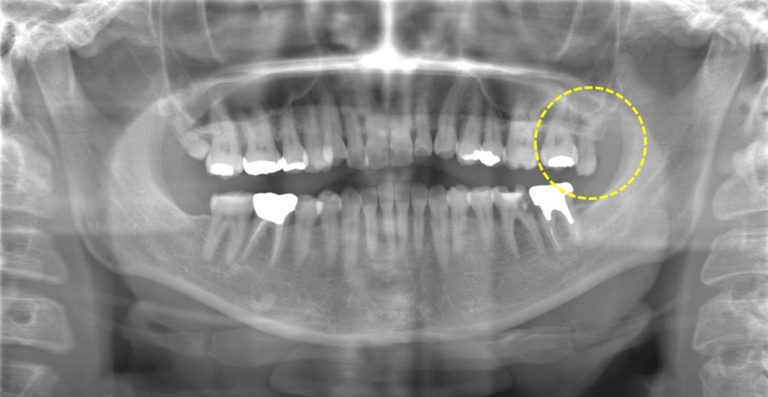

パノラマX線写真ではこう。

左下6番7番の治療後、もともと挺出して本人も気になっていた左上の親知らずを抜歯する流れになりました。

パノラマでは根っこの感じがあまりはっきりしません。